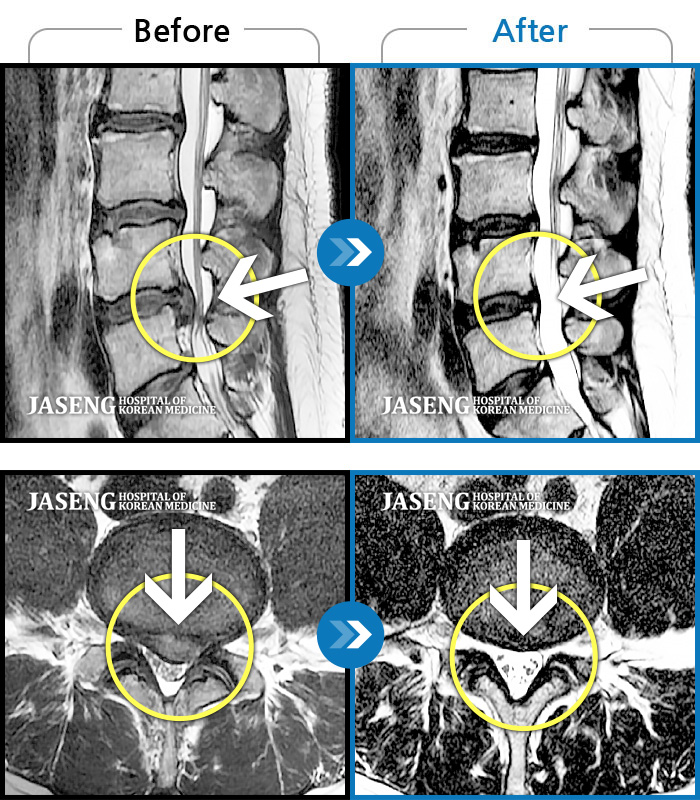

Before

After

환자에게 사전 동의를 받아 동일 조건에서 촬영되었습니다.

개인에 따라 치료 후 부작용이 발생할 수 있으니 의료진과 상담 후 치료를 진행하시기 바랍니다.

허리 통증이 심하고, 양측다리 하지 쪽으로 땡기고 저려요.

우측 허리 통증, 우측 하지 방사통, 근력저하 및 저림 증상을 동반하여 내원하였습니다.